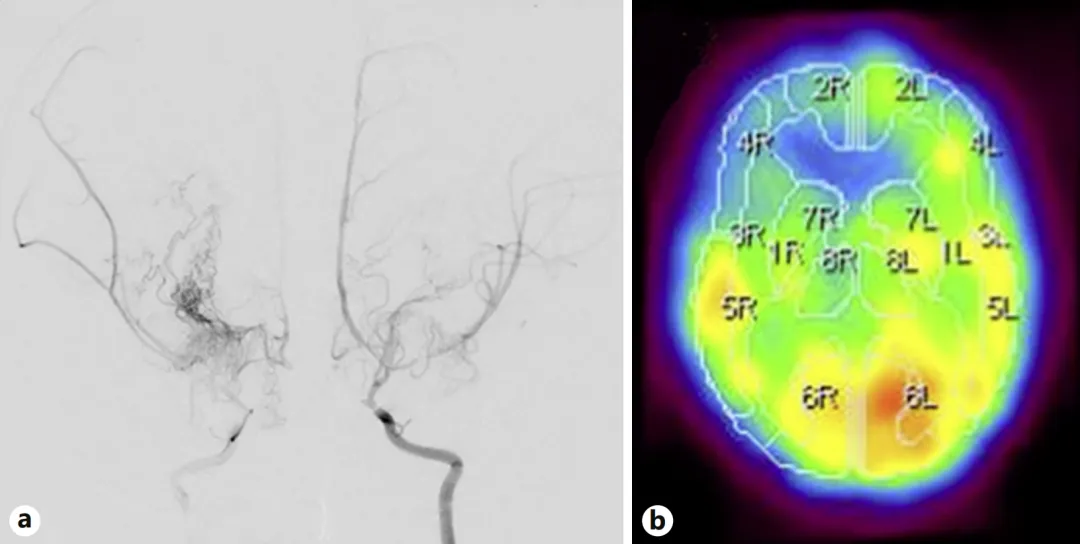

2岁女孩会突然摔倒,后来出现突发抽搐,检查发现:烟雾病合并脑梗死,双侧颈内动脉严重狭窄,以及右额叶脑血流明显减少。

图a,就像三条主干道同时堵车,脑组织正在“缺氧”的边缘挣扎。

图b,这解释了她反复猝倒的原因:大脑缺血时,身体会突然失去力量。